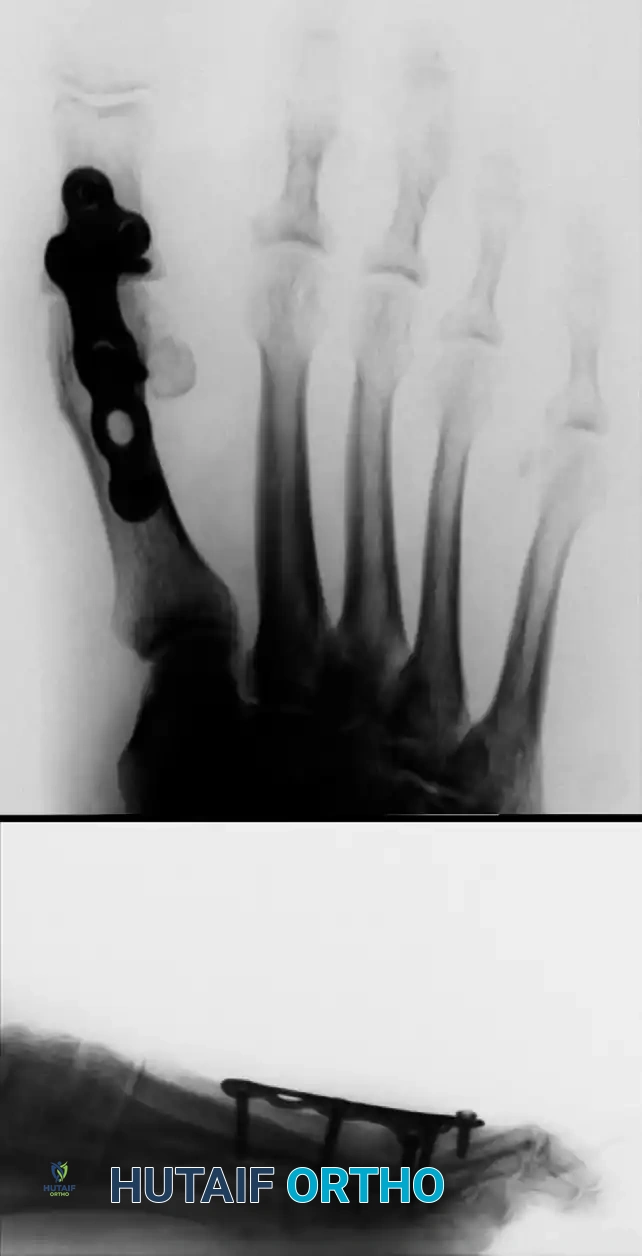

Once the joint surfaces are prepared, the MTP joint is reduced and fixed. While crossed lag screws are traditional, modern fixation often utilizes a dorsal locking plate with a compression screw for maximum rigidity, allowing for earlier weight-bearing.

Image

FIGURE 81-64: Anteroposterior (A) and lateral (B) radiographs of first metatarsophalangeal arthrodesis fixed with a dorsal plate and screws.